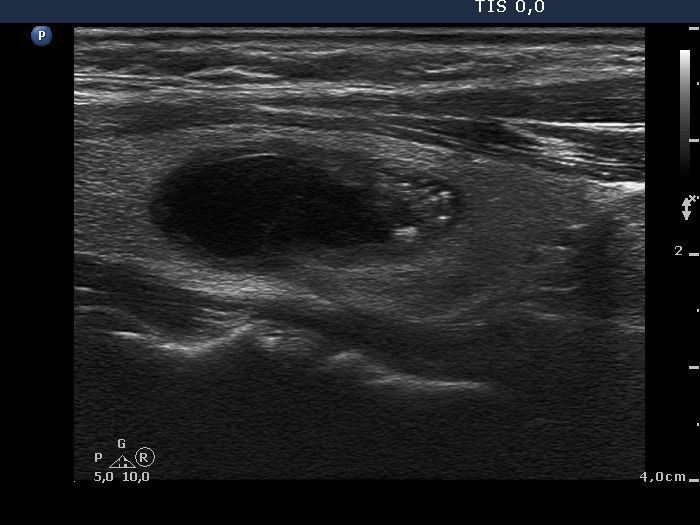

Follicular adenoma (histological diagnosis)

Before aspiration of 2 mL cystic fluid |

|

There are numerous hyperechogenic granules in the lower pole of the nodule. These figures might be confused with punctate echogenic foci (microcalcifications), as happened in this case. However, several have dorsal tail and therefore the remaining without a tail likely belong also to the same subgroup.